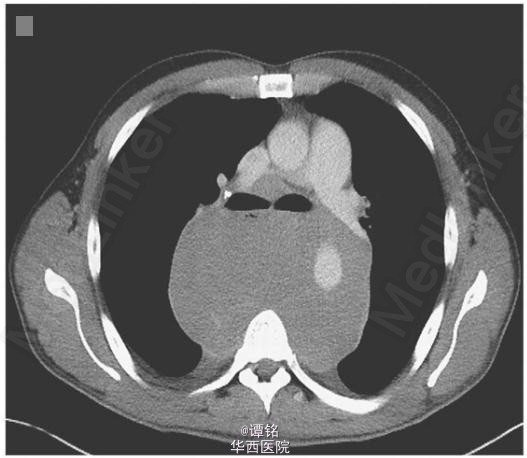

30岁男性,胸闷气紧、呼吸困难、吞咽困难、吞咽痛2月,体重减轻14kg。3年前查出I期睾丸精原细胞瘤,行睾丸切除术。此次胸片、CT显示后纵膈19*15*8cm的大肿物(图1,2),侵及邻近结构和降主动脉。hcG 4mIU/ml,LDH 1400/L,活检符合精原细胞瘤改变。采用博来霉素、依托泊苷、顺铂方案行3周期化疗,症状持续改善(随访三月,图3),见肿物逐渐缩小。10月后症状完全改善,后每4月长期随访。